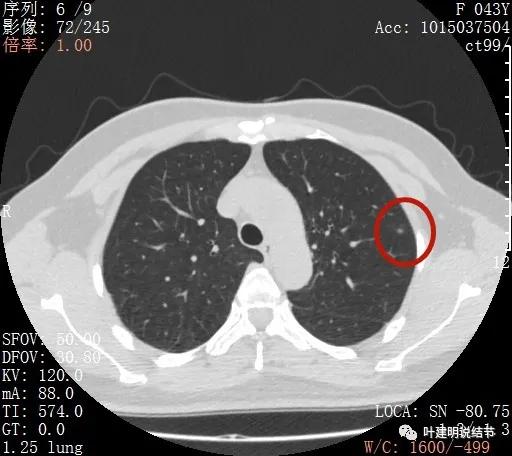

金华的某A,女性,今年43岁,检查发现左肺上叶结节2月余。其于当时说是在外院检查发现,到我门诊找我看过的(我是记不清楚了),大概是告诉她:考虑早期肺癌可能性大,但密度还低,边缘显模糊。让她再随访观察下再决定手术与否。这次送孩子上大学后,她马上来医院全面检查并若需要手术就决定手术了的。我们先来看她的平扫片子:

可见左肺上叶磨玻璃结节,边缘略显模糊,瘤肺边界不是很清,但总体上看,病灶轮廓仍是较为清楚的,而且有所层面有微小血管进入,病灶密度也不均匀,感觉有点杂乱。这种病灶如果随访了2个多月仍持续存在,也没多少变化的话,基本上要考虑肿瘤范畴的结节。为了看细节,我们建议其再查了靶扫描,图像如下: